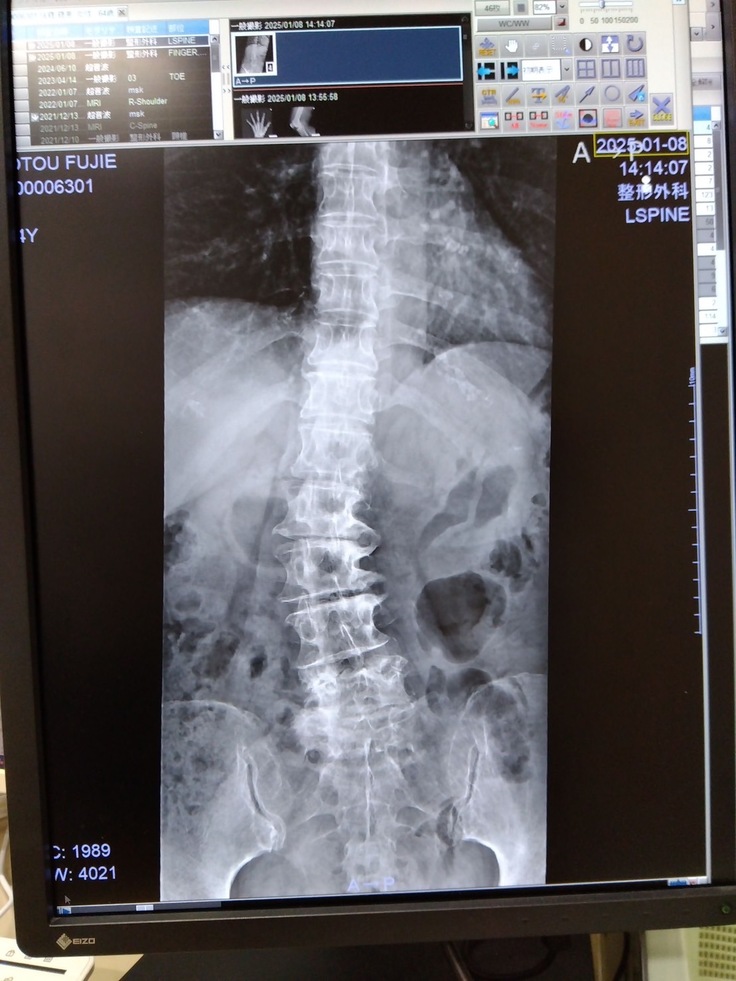

そして今回、病院の受診時に脛骨部分(足の骨)に腫瘍があることがわかりました。

背骨の変形も見られるのですが、骨腫瘍が特にひどく、このまま放置すると歩けなくなると言われ手術、入院をする運びになりました。